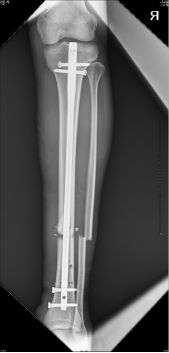

初步复位完成后,CO接骨机器人牵引下置入髓内钉

术后影像资料